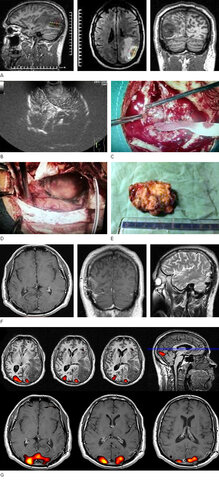

• La TC se utiliza para detectar un tumor cerebral por primera vez.

La TC se utiliza para detectar un tumor cerebral por primera vez.